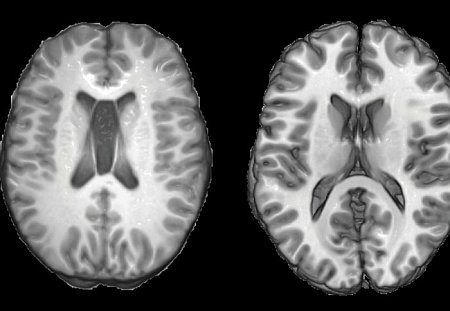

Scansioni MRI del cervello di un paziente con trauma cranico (sinistra) e di una persona sana (destra).Le persone che hanno subito gravi lesioni alla testa mostrano cambiamenti nella struttura del cervello simili a quelli presenti negli anziani, secondo un nuovo studio.

Lo studio, pubblicato nel numero di aprile di Annals of Neurology, ha usato la risonanza magnetica per immagini (MRI) per studiare i cambiamenti della struttura del cervello. I ricercatori hanno impiegato un algoritmo di apprendimento automatico per sviluppare un programma per computer che può riconoscere le differenze legate all'età nel volume della materia bianca e della materia grigia, in diverse parti del cervello.

Nei soggetti sani la differenza media tra l'età prevista e l'età reale era pari a zero. Nei pazienti con trauma cranico, la differenza era significativamente più alta, con una discrepanza maggiore nei pazienti con lesioni più gravi. Le differenze nell'età prevista sono state associate ai disturbi cognitivi, come una memoria scarsa e tempi lenti di reazione.